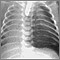

The health care provider will listen to your breathing with a stethoscope. If you have a collapsed lung, there are decreased breath sounds or no breath sounds on the affected side. You may also have low blood pressure.

- Chest x-ray